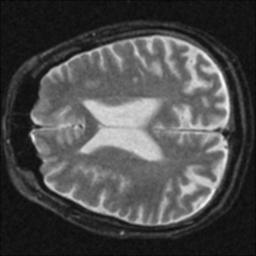

The resolution loss is measured relative to the FWHM of the noisy image, consequently its resolution loss is 0%. Interesting is that the CNR mirrors changes in the SNR, as expected. Also interesting is that the contrast filter reduced the SNR dramatically while actually improving the image resolution. The following images were obtained after filtering:

Median Filter